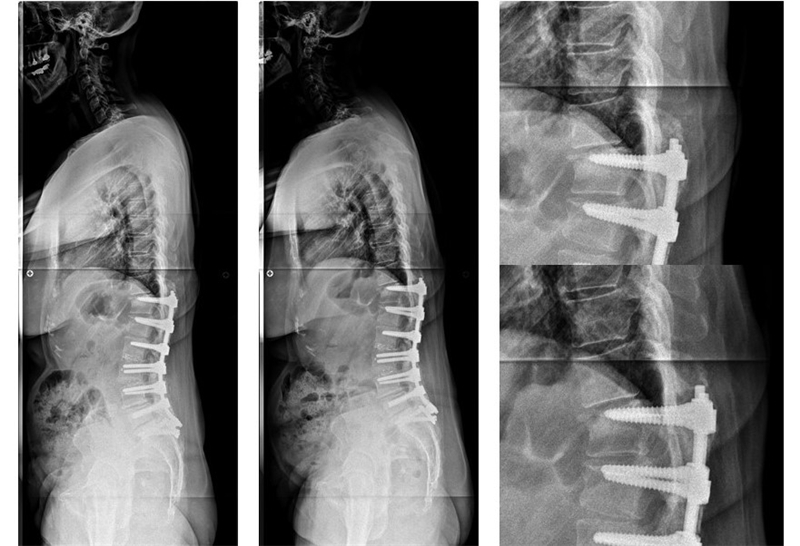

在手术治疗2型患者时建议行短节段固定将腰椎矢状面序列维持为2型。若2型患者合并胸椎后凸畸形,建议在L4行PSO截骨矫正至1型序列;若仍维持为2型则有胸椎后凸减小的可能;若矫正至腰椎前凸较大的3型,术后发生PJK的风险较高。

2型患者合并胸椎后凸畸形,建议在L4行PSO截骨矫正至1型序列

在整体后凸畸形的病例中,建议在L4行PSO截骨将矢状面序列矫正至1型或2型,此时应注意避免矫正至3型,因骨盆将发生前倾,继而导致矢状面向前失平衡

整体后凸畸形时在L4行PSO截骨将矢状面序列矫正至1型

若骨盆后倾的2型患者合并整体后凸畸形时,建议在L3或L4行较大的PSO截骨,并行长节段融合,将脊柱矫正至3型或4型。

PI较大的2型患者合并整体后凸畸形,将脊柱矫正至3型或4型